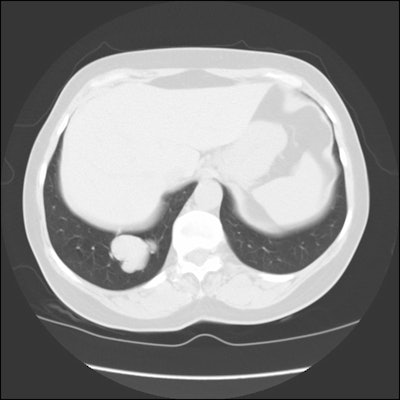

CT and helical CT can also be used to demonstrate the presence of

a feeding artery. Most of these lesions have a single feeding

artery and draining vein, however, they may be multiple. Spiral CT

with contiguous images and overlapping reconstructions is more

sensitive than angiography for detecting and displaying the

vascular connections of pulmonary AVM's- the angio-architecture

can be identified in 76 to 95% of lesions [5]. Contrast

enhancement of the lesion may not be seen if the lesion is

thrombosed.

| CT from the patient shown

above: Click image to view cine file. |